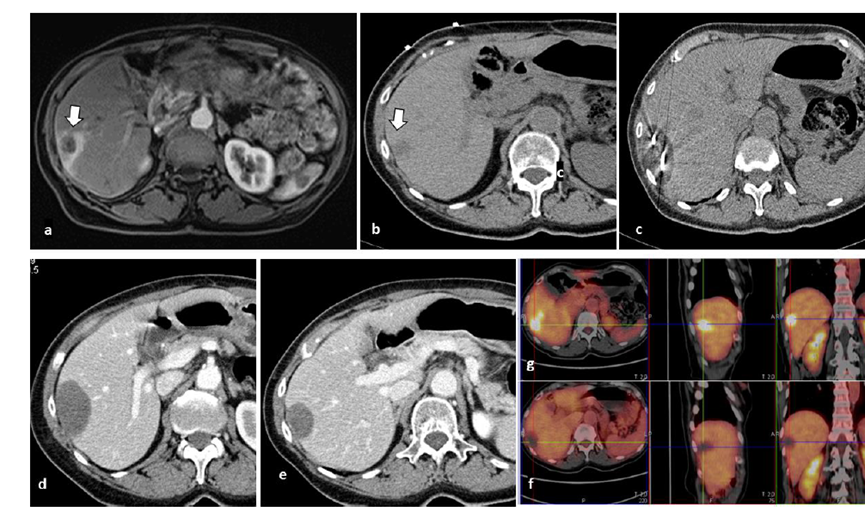

冷凍消融膽囊附近腫瘤病灶

(A)動(dòng)脈期 MRI 顯示膽囊附近有外周增強(qiáng)病變(箭頭)。

(B)手術(shù)過程中 CT 顯示冷凍探針位于病灶內(nèi)。

(C)消融后,術(shù)后 1 個(gè)月CT 顯示完全消融(箭頭)。

(A)動(dòng)脈期CT圖像顯示有一個(gè)包膜下結(jié)節(jié)(箭頭)。(B)門靜脈期CT圖像顯示病灶區(qū)(箭頭)。(C) 在手術(shù)過程中的CT顯示一個(gè)冷凍探針位于病灶內(nèi)。(D)消融后,術(shù)后1個(gè)月影像CT顯示完全消融。患者在手術(shù)及住院期間無并發(fā)癥及重大并發(fā)癥發(fā)生。隨訪時(shí)間中位數(shù)為7個(gè)月(范圍:3-12個(gè)月),隨訪期間患者無局部腫瘤進(jìn)展或死亡。

技術(shù)成功率為100%,本研究中77.8%(7/9)的患者達(dá)到了完全消融,輔助局部治療后,所有患者均完全消融。

膽囊附近轉(zhuǎn)移灶(來自子宮頸癌)的冷凍消融術(shù)(A)門靜脈期 CT 圖像顯示膽囊附近有病變(箭頭)。(C) 手術(shù)過程中CT 顯示冷凍探針位于病灶內(nèi)。(D)消融手術(shù)后 1 個(gè)月CT 顯示完全消融。

79 歲男性,肝轉(zhuǎn)移(結(jié)直腸癌)腫瘤的完全消融病例

( a ) 軸向 MRI 和 ( b ) 軸向 CT 顯示肝S8段有一個(gè)16mm的病灶,鄰近肝緣。( c )冷凍消融期間CT顯示放置了2個(gè)冷凍探針,低密度冰球包圍病灶。(d)術(shù)后1個(gè)月隨訪 CT顯示冰球?qū)?yīng)的壞死區(qū)域,未見復(fù)發(fā)。(e)術(shù)后6個(gè)月的CT,壞死區(qū)域縮小,未見復(fù)發(fā)。(f)與基線影像(g)相比,12個(gè)月后的FDG-PET/CT顯示未見FDG攝取。